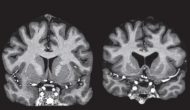

羅氏亨廷頓ASO療法三期臨床叫停

今天羅氏宣布從Ionis收購(gòu)的亨廷頓癥反譯核酸療法 tominersen?在三期臨床 GENERATION HD1試驗(yàn)被叫停。